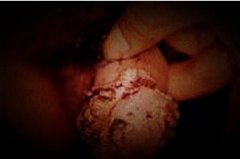

石家庄九州皮肤病医院 > 尖锐湿疣 > > > 尖锐湿疣患者生活中应做好哪些护理?尖锐湿疣是可以带给患者生殖器严重的损害,而且也是可以给患者的生活带来严重的损害,因此对于尖锐湿疣建议患者能够尽早的选择专业的医院去治疗,在临床上尖锐湿疣的确是比较顽固易复发,但是只要患者能够科学的治疗还是可以彻底根治的,在临床上建议患者选择方法的时候一定要慎重,以免患者的治疗会再次复发。

尖锐湿疣患者生活中应做好哪些护理?尖锐湿疣是能够给患者治疗带来不小的压力,因为尖锐湿疣虽然现在有不少的治疗方法,但是患者的治疗却多数还是容易复发的,因此严格来说患者的治疗压力还是比较大的,而得了尖锐湿疣患者应当选择专业的医院和科学的方法去治疗,另外患者在生活中也要注意做好自身的辅助,在生活中可是一定要避免自己免疫力降低的,要防止传染等等。